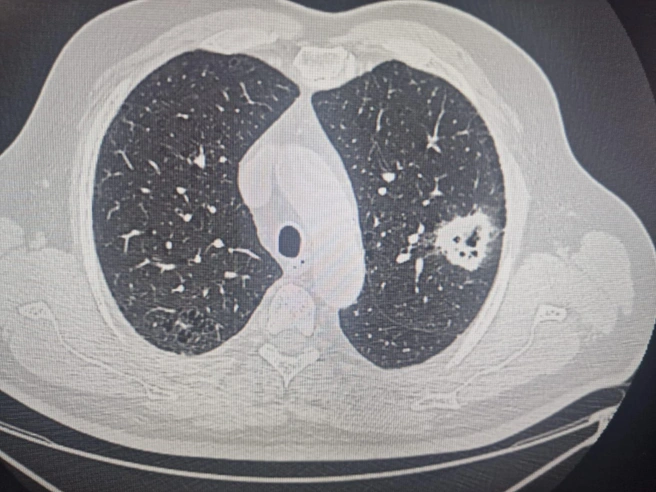

Заведующий онкологическим отделением № 3 Новосибирского областного клинического онкологического диспансера Вадим Козлов рассказал, что у одного из его пациентов выявили рак правого лёгкого три года назад. Врачам удалось сохранить большую часть лёгких — обычно в таких случаях орган удаляют полностью.

В течение следующих двух лет пациент находился под контролем врачей. У мужчины развился рак — на этот раз в левом лёгком. Так как заболевание выявили на очень ранней стадии, операция прошла успешно. Помогло и то, что в первый раз лёгкое удалось сохранить.

В течение года пациент был в ремиссии, но позже рак вновь начал прогрессировать. Сейчас новосибирец находится на химиотерапии, добавил Вадим Козлов.